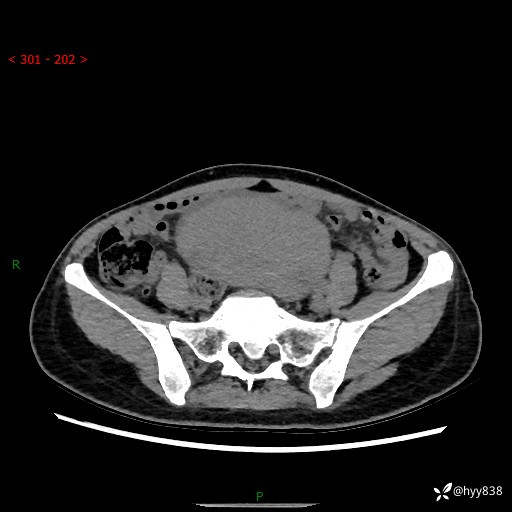

【患者信息】:女,50岁

【主诉】:外院超声发现腹盆肿块,为进一步诊治来我院,门诊已“盆腔肿块”收入院。

腹盆CT平扫+增强

【临床诊断】:盆腔肿瘤